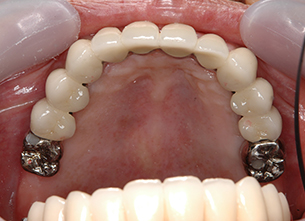

症例1 : 上下顎無菌顎症例

69歳、男性。

• 上顎は両側サイナスリフトと同時に即時荷重を行った。

• 下顎は抜歯即時埋入即時荷重を行った。

• 最終補綴物は、チタンのP.I.B.とM.B.のコンビネーションで修復した。

• 本症例の要旨は第39回日本口腔インプラント学会(大阪)にて症例報告した。